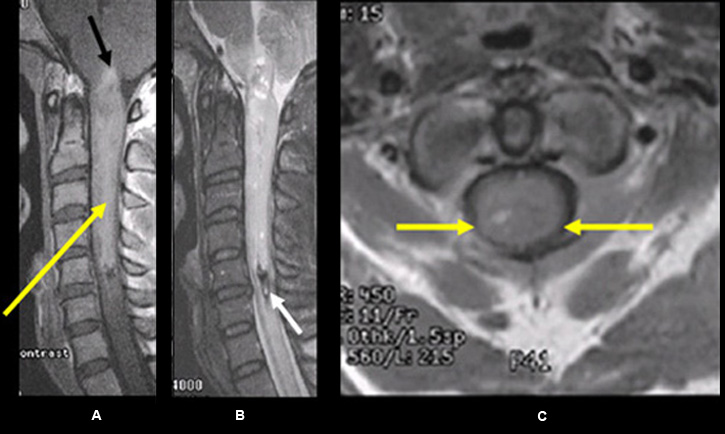

Ependymoma of the Cervical Cord

Figure 5

Imaging findings: Figure 5

- Post-contrast (C+) sagittal T1wtd. MRI

- sausage-shaped intensely enhancing tumor (yellow arrow) is seen within the upper cervical cord extending from just above the craniocervical junction with involvement of the dorsal medulla (black arrow) down to C5 level

- Sagittal T2 wtd. MRI image of the C spine

- small amount of old hemosiderin blood product is better seen on T2 wtd. image as an area of dark signal intensity within the edge of the tumor (white arrow)

- Post-contrast axial T1wtd. MRI (C+)

- central location of tumor (yellow arrows) is better appreciated on axial post-contrast image

Final impression:

- This is intramedullary tumor because the cord has expanded in both sagittal and axial projections.

- It is centrally located.

- Intensely enhancing tumor.

Imaging findings are consistent with ependymoma.